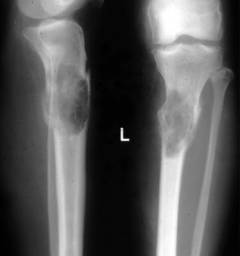

Рентгенография костей – метод рентгенологического исследования для выявления поражений костей и подтверждения диагноза «миеломная болезнь». Проводятся снимки с передней и боковой проекции.

Изменения на рентгеновских снимках могут включать:

- признаки остеопороза

- «дырявый череп» – очаги разрушения в черепе

- отверстия в плечевых костях

- «изъеденные молью» ребра и лопатки

- сжатые позвонки

При рентгенографии запрещено использование контрастных веществ, так как йод может повредить почки.